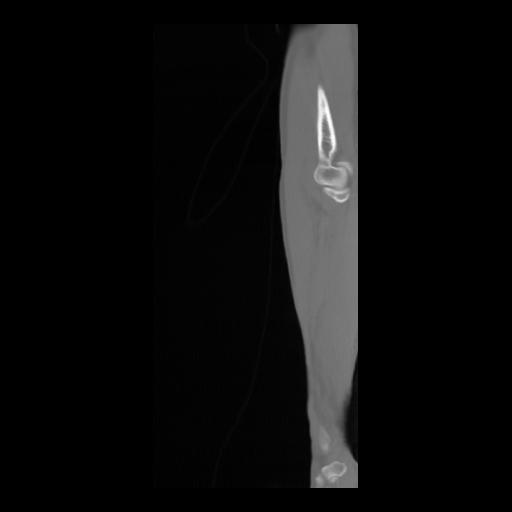

36 CUERPO,CE,Sagittal,3.000,CUERPO,Sagittal,